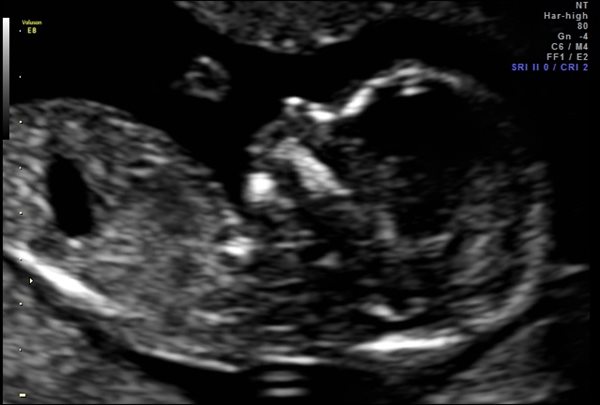

Let the SoR know your views on covid-19 arrangements for support person access and videoconferencing of obstetric scans

SoR members are reporting rumours of a new deadline for enabling support person attendance at all pregnancy examinations

Sonographers have faced backlash when partners excluded from examinations